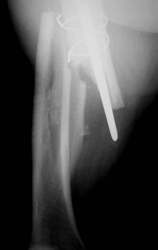

Ein Femurnagel wurde so zugerichtet, dass mit ihm die Prothesenspitze in einer Länge von 8 cm aufgefädelt wurde. Der Nagel wurde durch das Knie hindurch eingebracht. Distal wurde der Nagel verriegelt. Belastungsstabilität lag vor.